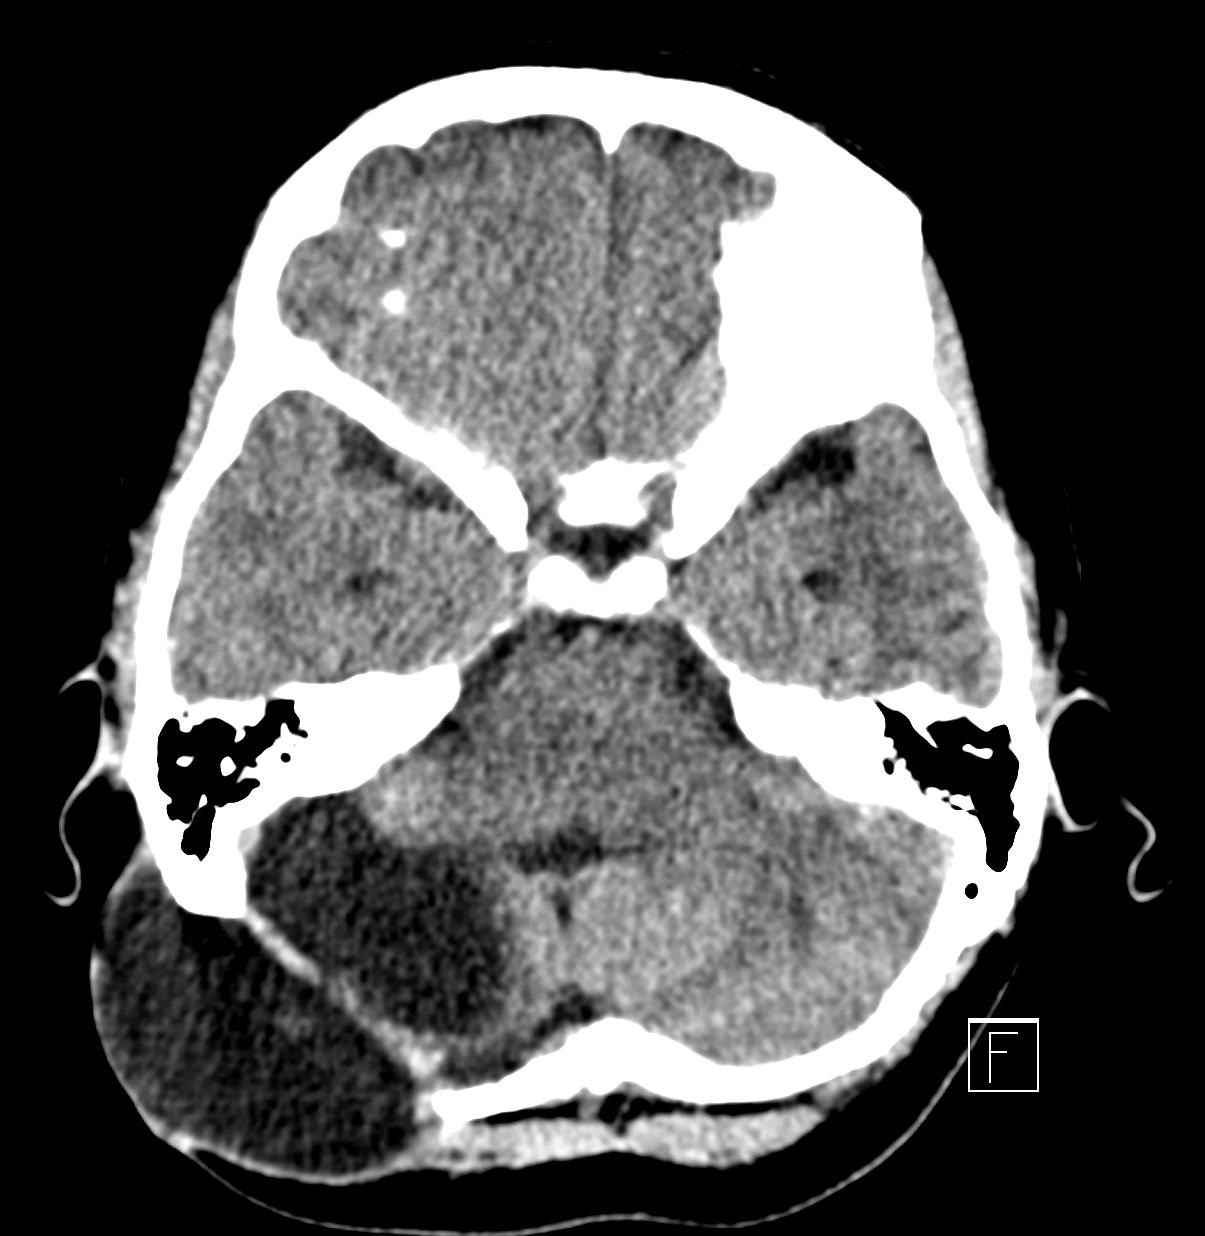

Bildgebung

Ein Liquorkissen kann durch die klinische Untersuchung diagnostiziert werden als auch in einer CT oder MRT Bildgebung dargestellt werden.